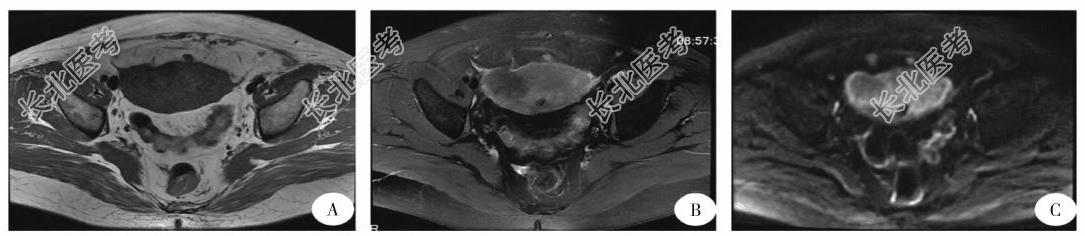

- [材料题] 患者,女,55岁,因“间断性下腹痛3年,阴道少量流血5d”就诊。患者曾因异位妊娠行经腹左侧输卵管切除术。妇检:子宫超手拳大,质地硬,表面光滑,活动度一般,压痛阳性,双侧附件区未触及异常。盆腔彩超:宫体部见范围约8.6cm×8.6cm×5.0cm不均匀低回声,边界不清,形态不规则,局部略呈团状,可检出血流信号。盆腔增强MRI:子宫底及前壁肌层可见团块影,T1WI呈稍低信号,T2WI呈稍高信号,dWI序列呈高信号(图a~C)。考虑子宫占位病变,累及结合带,恶性可能大。行诊刮术,病理回报:(子宫内膜)考虑梭形细胞肿瘤。遂行腹腔镜全子宫及右侧附件切除术、左侧卵巢切除术、部分大网膜切除术及大网膜粘连松解术。术程顺利,标本装取物袋于阴道切碎分块取出,取标本时间约40MIN。术后病理:子宫炎性肌纤维母细胞肿瘤。